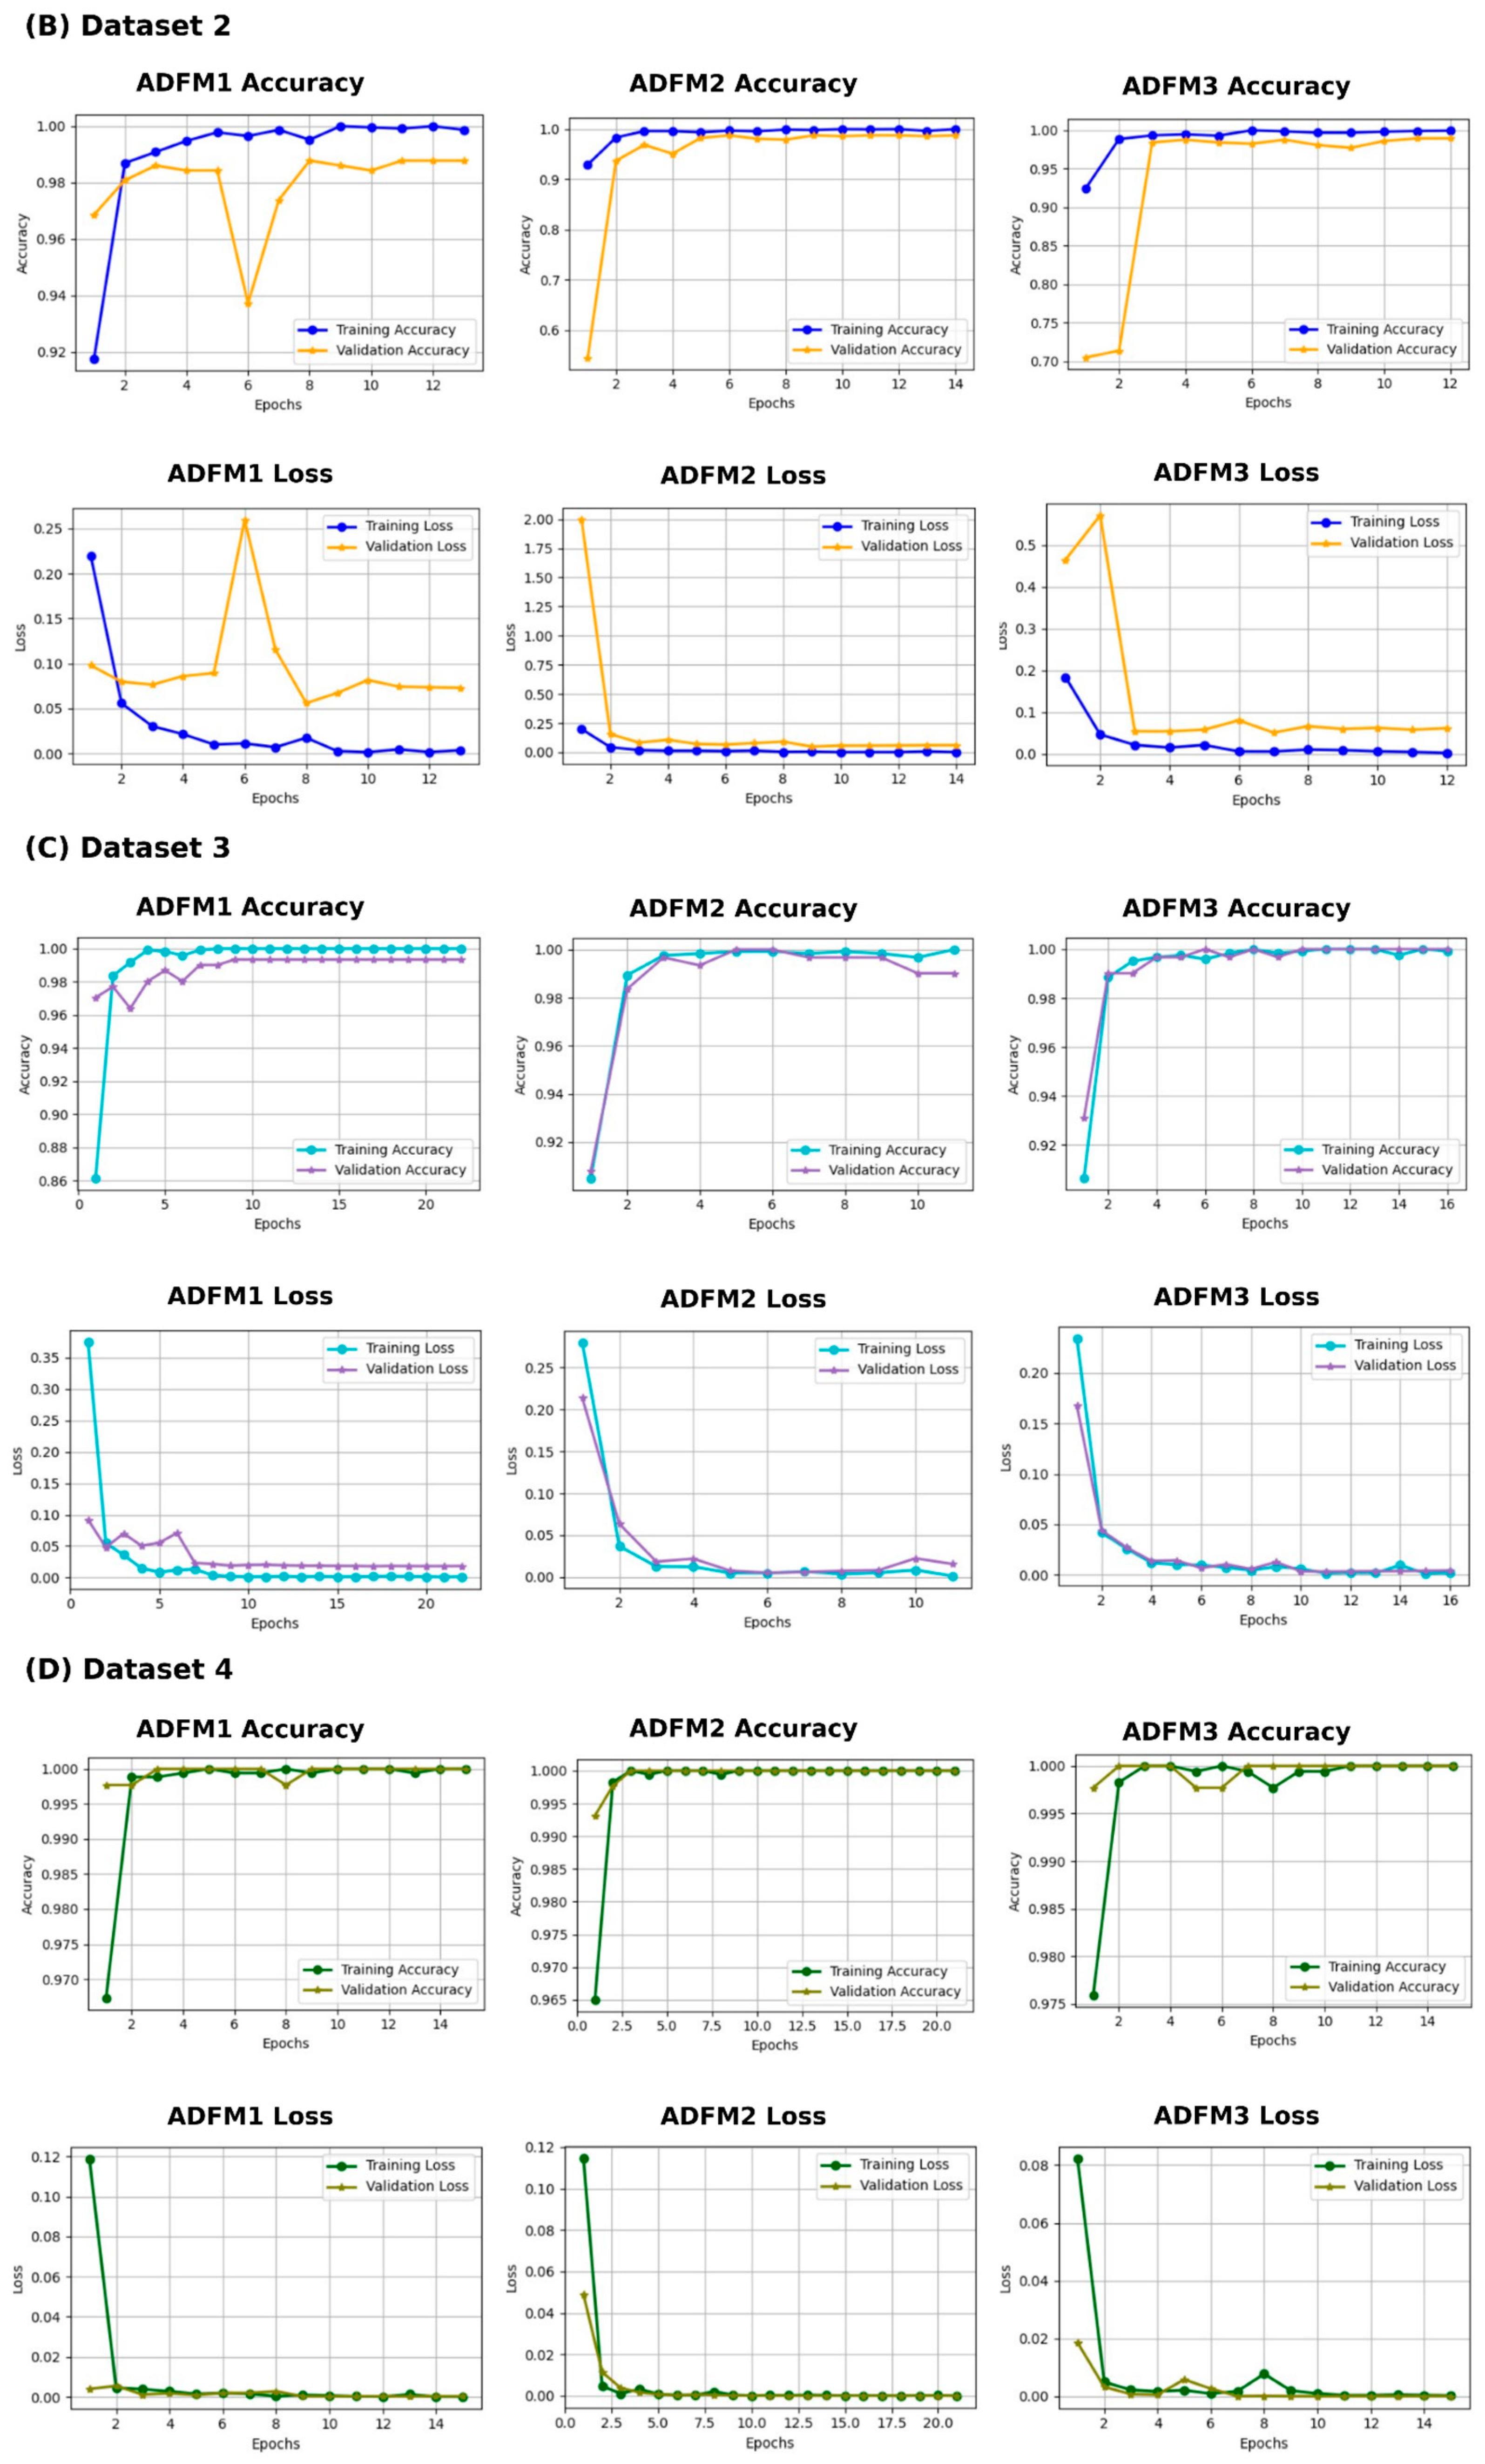

3.4. Experimental Results

3.5. K-Fold Cross-Validation for ADFMs